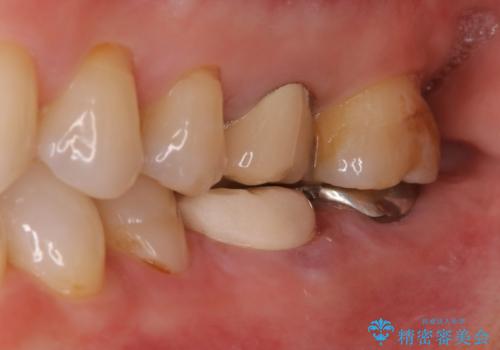

他院で仮歯までしたが、放置していたためセラミック入れたい セラミック治療

- 他院で、仮歯にしたがセラミックの値段が高すぎると思ったため治療相談も含めて来院された患者様です。

仮歯を新調させていただき、再度虫歯治療を行なって、歯の形を作りセラミックを入れさせていただきました。

フルジルコニアクラウン 7万円(税抜)

仮歯 1万円

にて治療させていただきました。色に関しても喜んでいただき満足されていました。